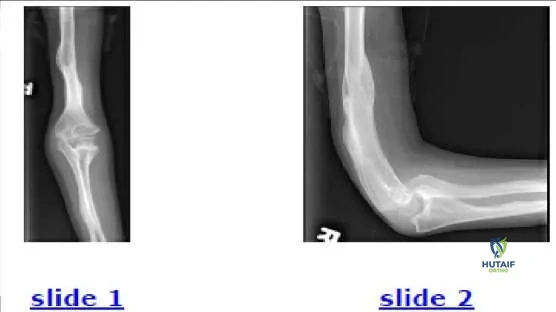

The 9-year-old patient presented in the radiographs (Slide 1, Slide 2) should be diagnosed with:

Correct Answer: Osteogenesis imperfecta

Explanation:

This patient has type V osteogenesis imperfecta, which is characterized by hereditary radial head dislocation in 86% of patients (this patients mother

and brother also have the condition bilaterally) as well as heterotopic calcification, osseous fragility, and scoliosis. Dislocation of the radial head occurs less often (0%-29%) in the other types of osteogenesis imperfecta and is linked to angular deformation of the long bones. The signs of osteogenesis imperfecta in this patient include thin long bones, several healed fractures, and angular deformations.